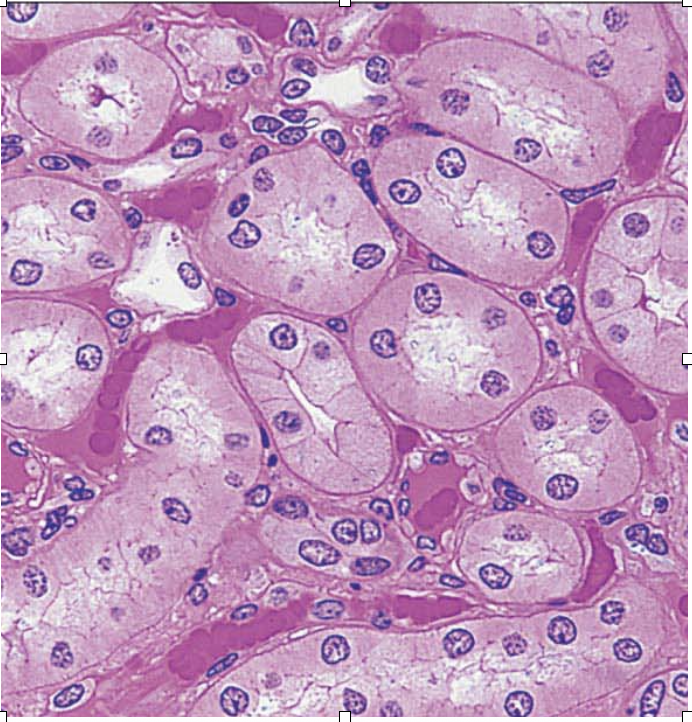

Skeletal Muscle